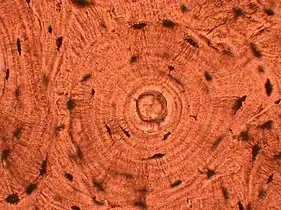

Cartwheel pattern: Center points that radiate cells or connective tissue outward